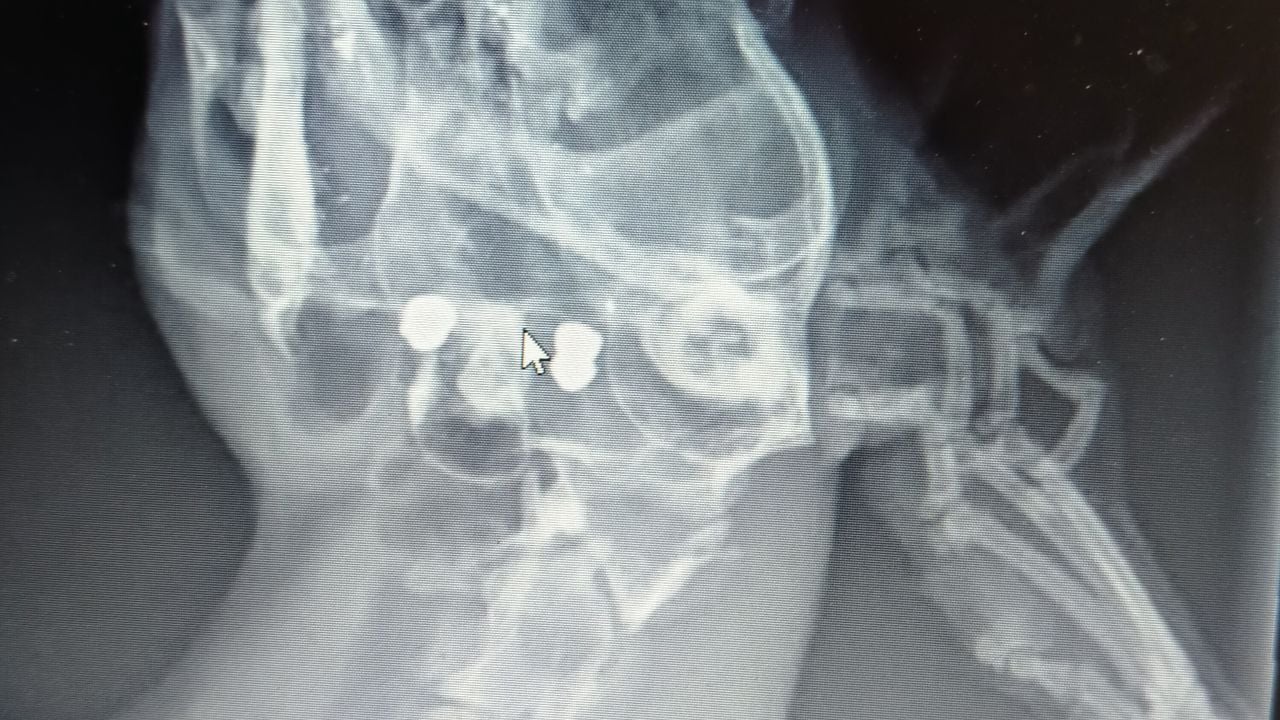

“Een van haar poten hing nog maar aan een paar pezen, omdat ze vast had gezeten in een klem.” Op röntgenfoto’s werd duidelijk dat het dier ook twee kogels in haar lichaam had.

“Ze was twee keer tegen haar kopje geschoten, waarschijnlijk om haar uit die klem te kunnen halen en daarna is ze voor dood achtergelaten. Dat beestje heeft ontzettend geleden. Echt verschrikkelijk.”